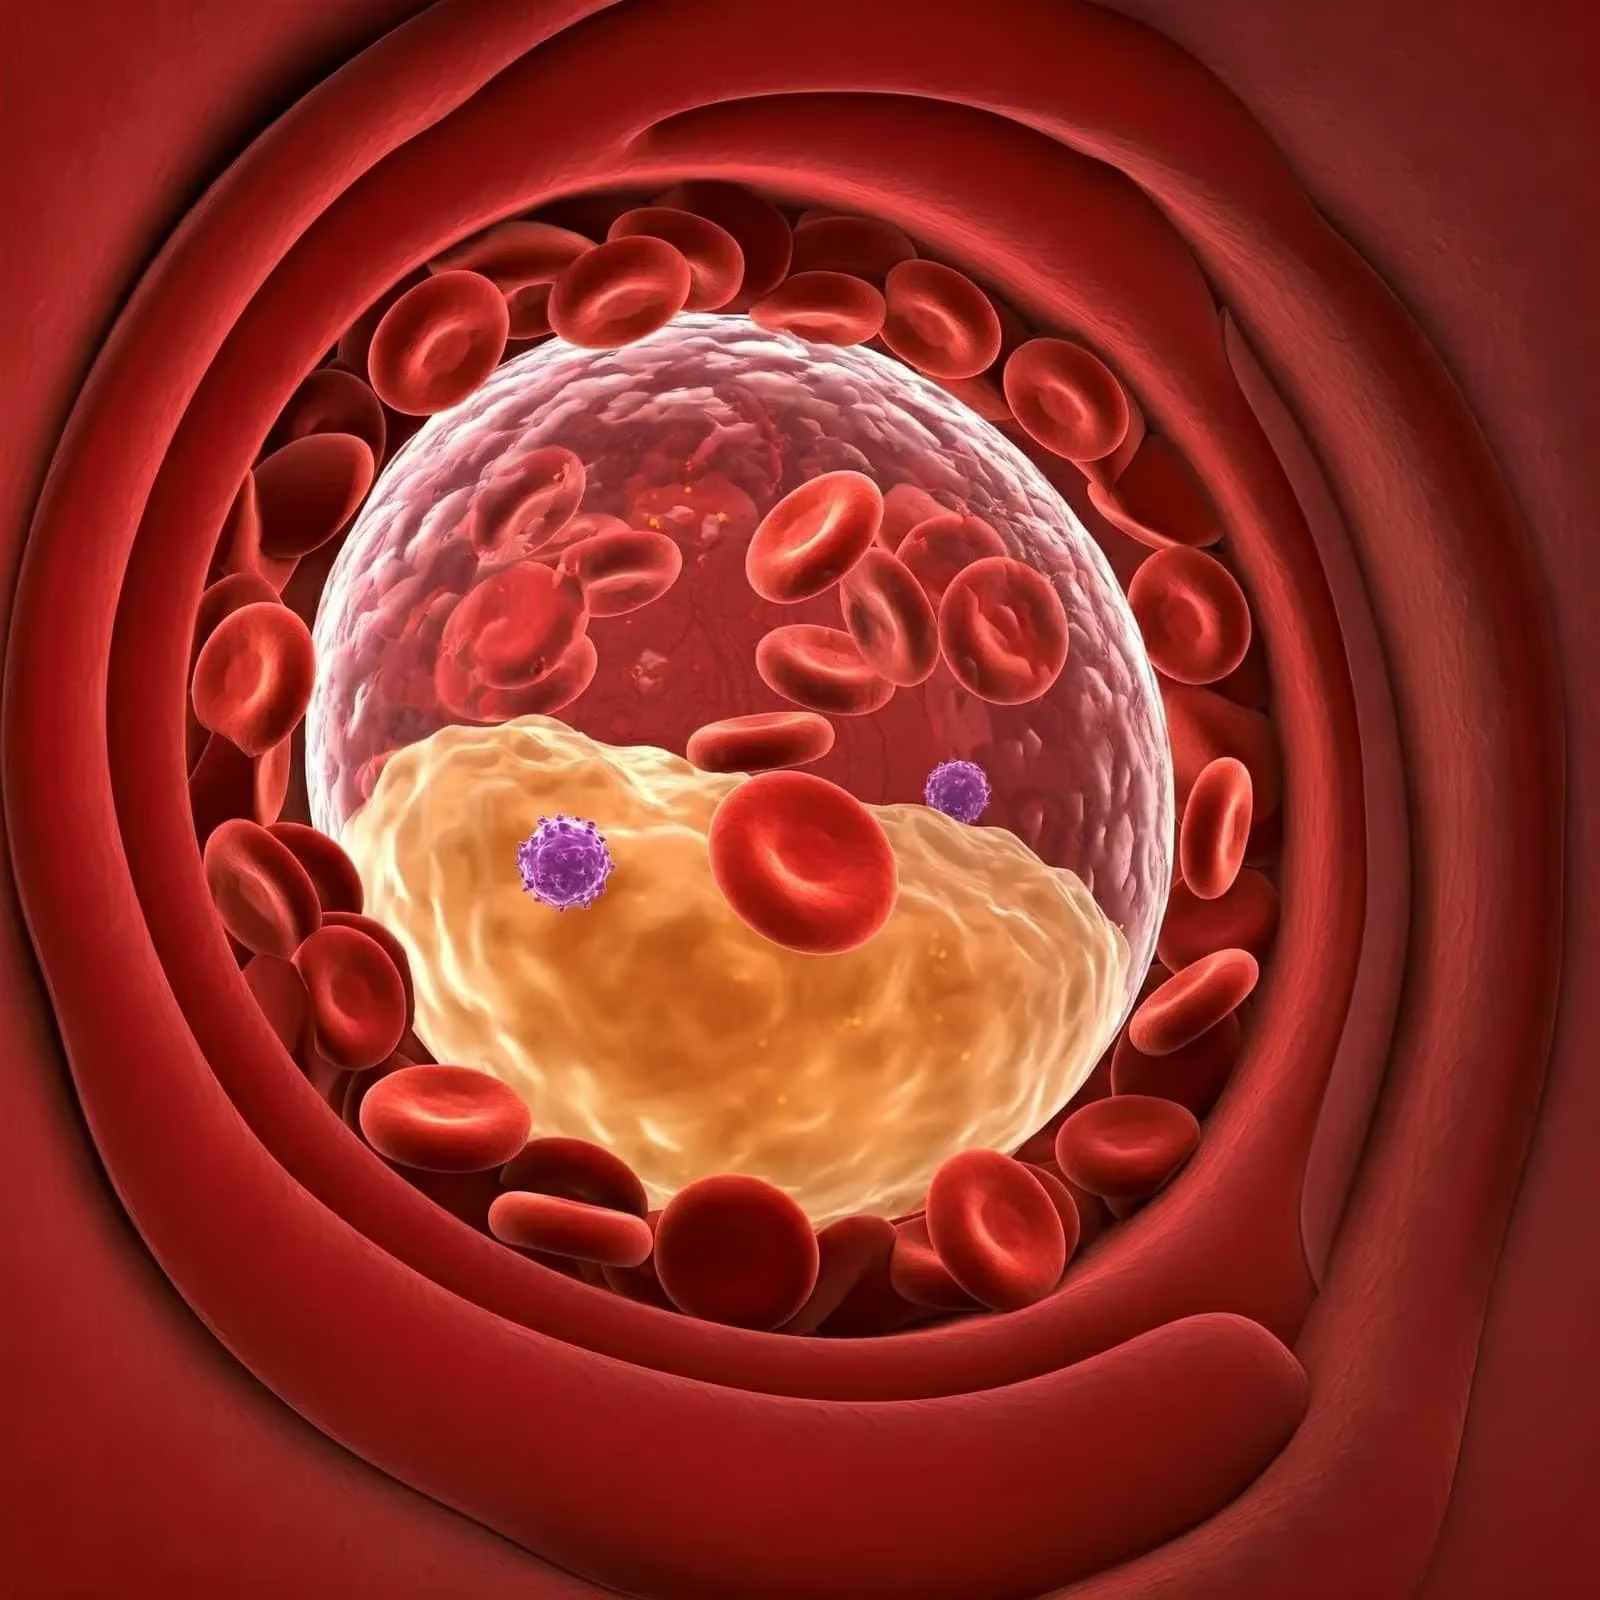

Introduction Dermal filler injections have become a cornerstone of aesthetic medicine, providing a minimally invasive solution for rejuvenating facial features,…